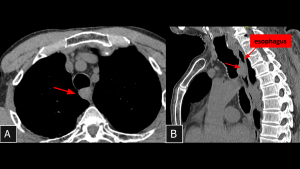

Fig 18: Case 19 – Giant Fibrovascular Polyp of the Esophagus:

Panels A and B (Sagittal and Coronal CT, respectively) demonstrate a large intraluminal lesion originating in the cervical esophagus, at the level of the cricopharyngeus muscle. The mass extends distally and presents heterogeneous attenuation.

SYSTEMATIC APPROACH: 1. Age: Elderly males. | 2. Morphology: Sausage-like intraluminal mass with macroscopic fat. | 3. Enhancement: Heterogeneous (vessels/fibrous septa). | 4. Relevant Anatomical Relationships: Originates in cervical esophagus (Cricopharyngeus); extends distally.